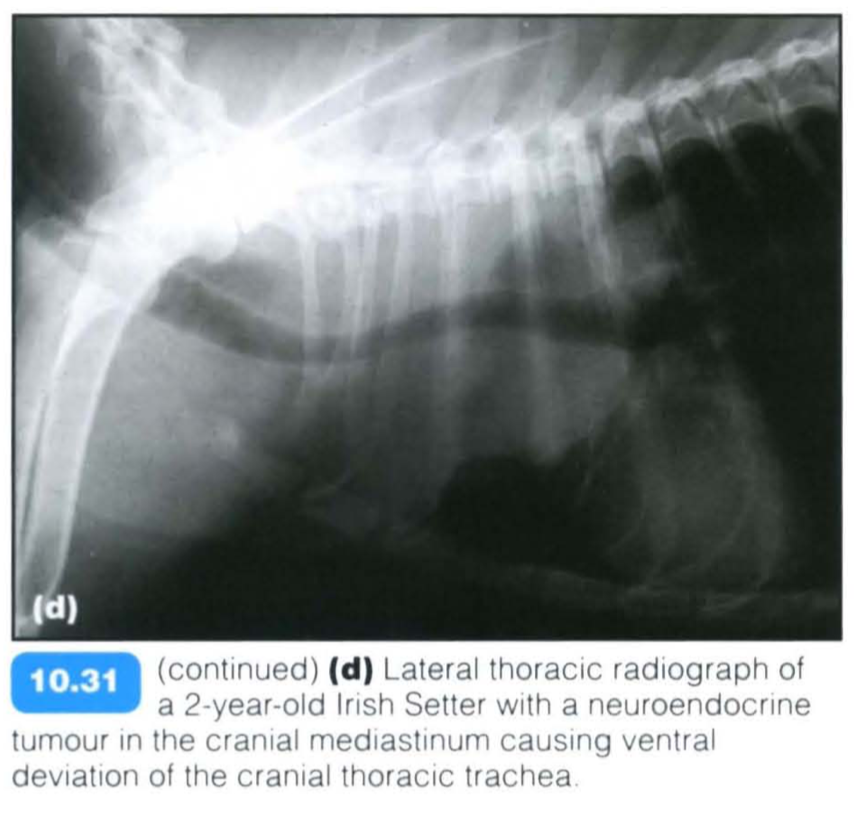

Ventral Tracheal Deviation

Neuroendocrine cells are characterized by their ability to produce and secrete a neuromodulator, transmitter, or hormone. Examples of NETs include carcinoids, gastroenterohepatic tumors (gastrinoma, insulinoma, glucagonoma), pheochromocytoma of the adrenal gland, medullary carcinoma of the thyroid gland, some pituitary tumors, small-cell lung cancer, multiple endocrine neoplasia (MEN types 1 and 2), and tumors of the chemoreceptor organs.